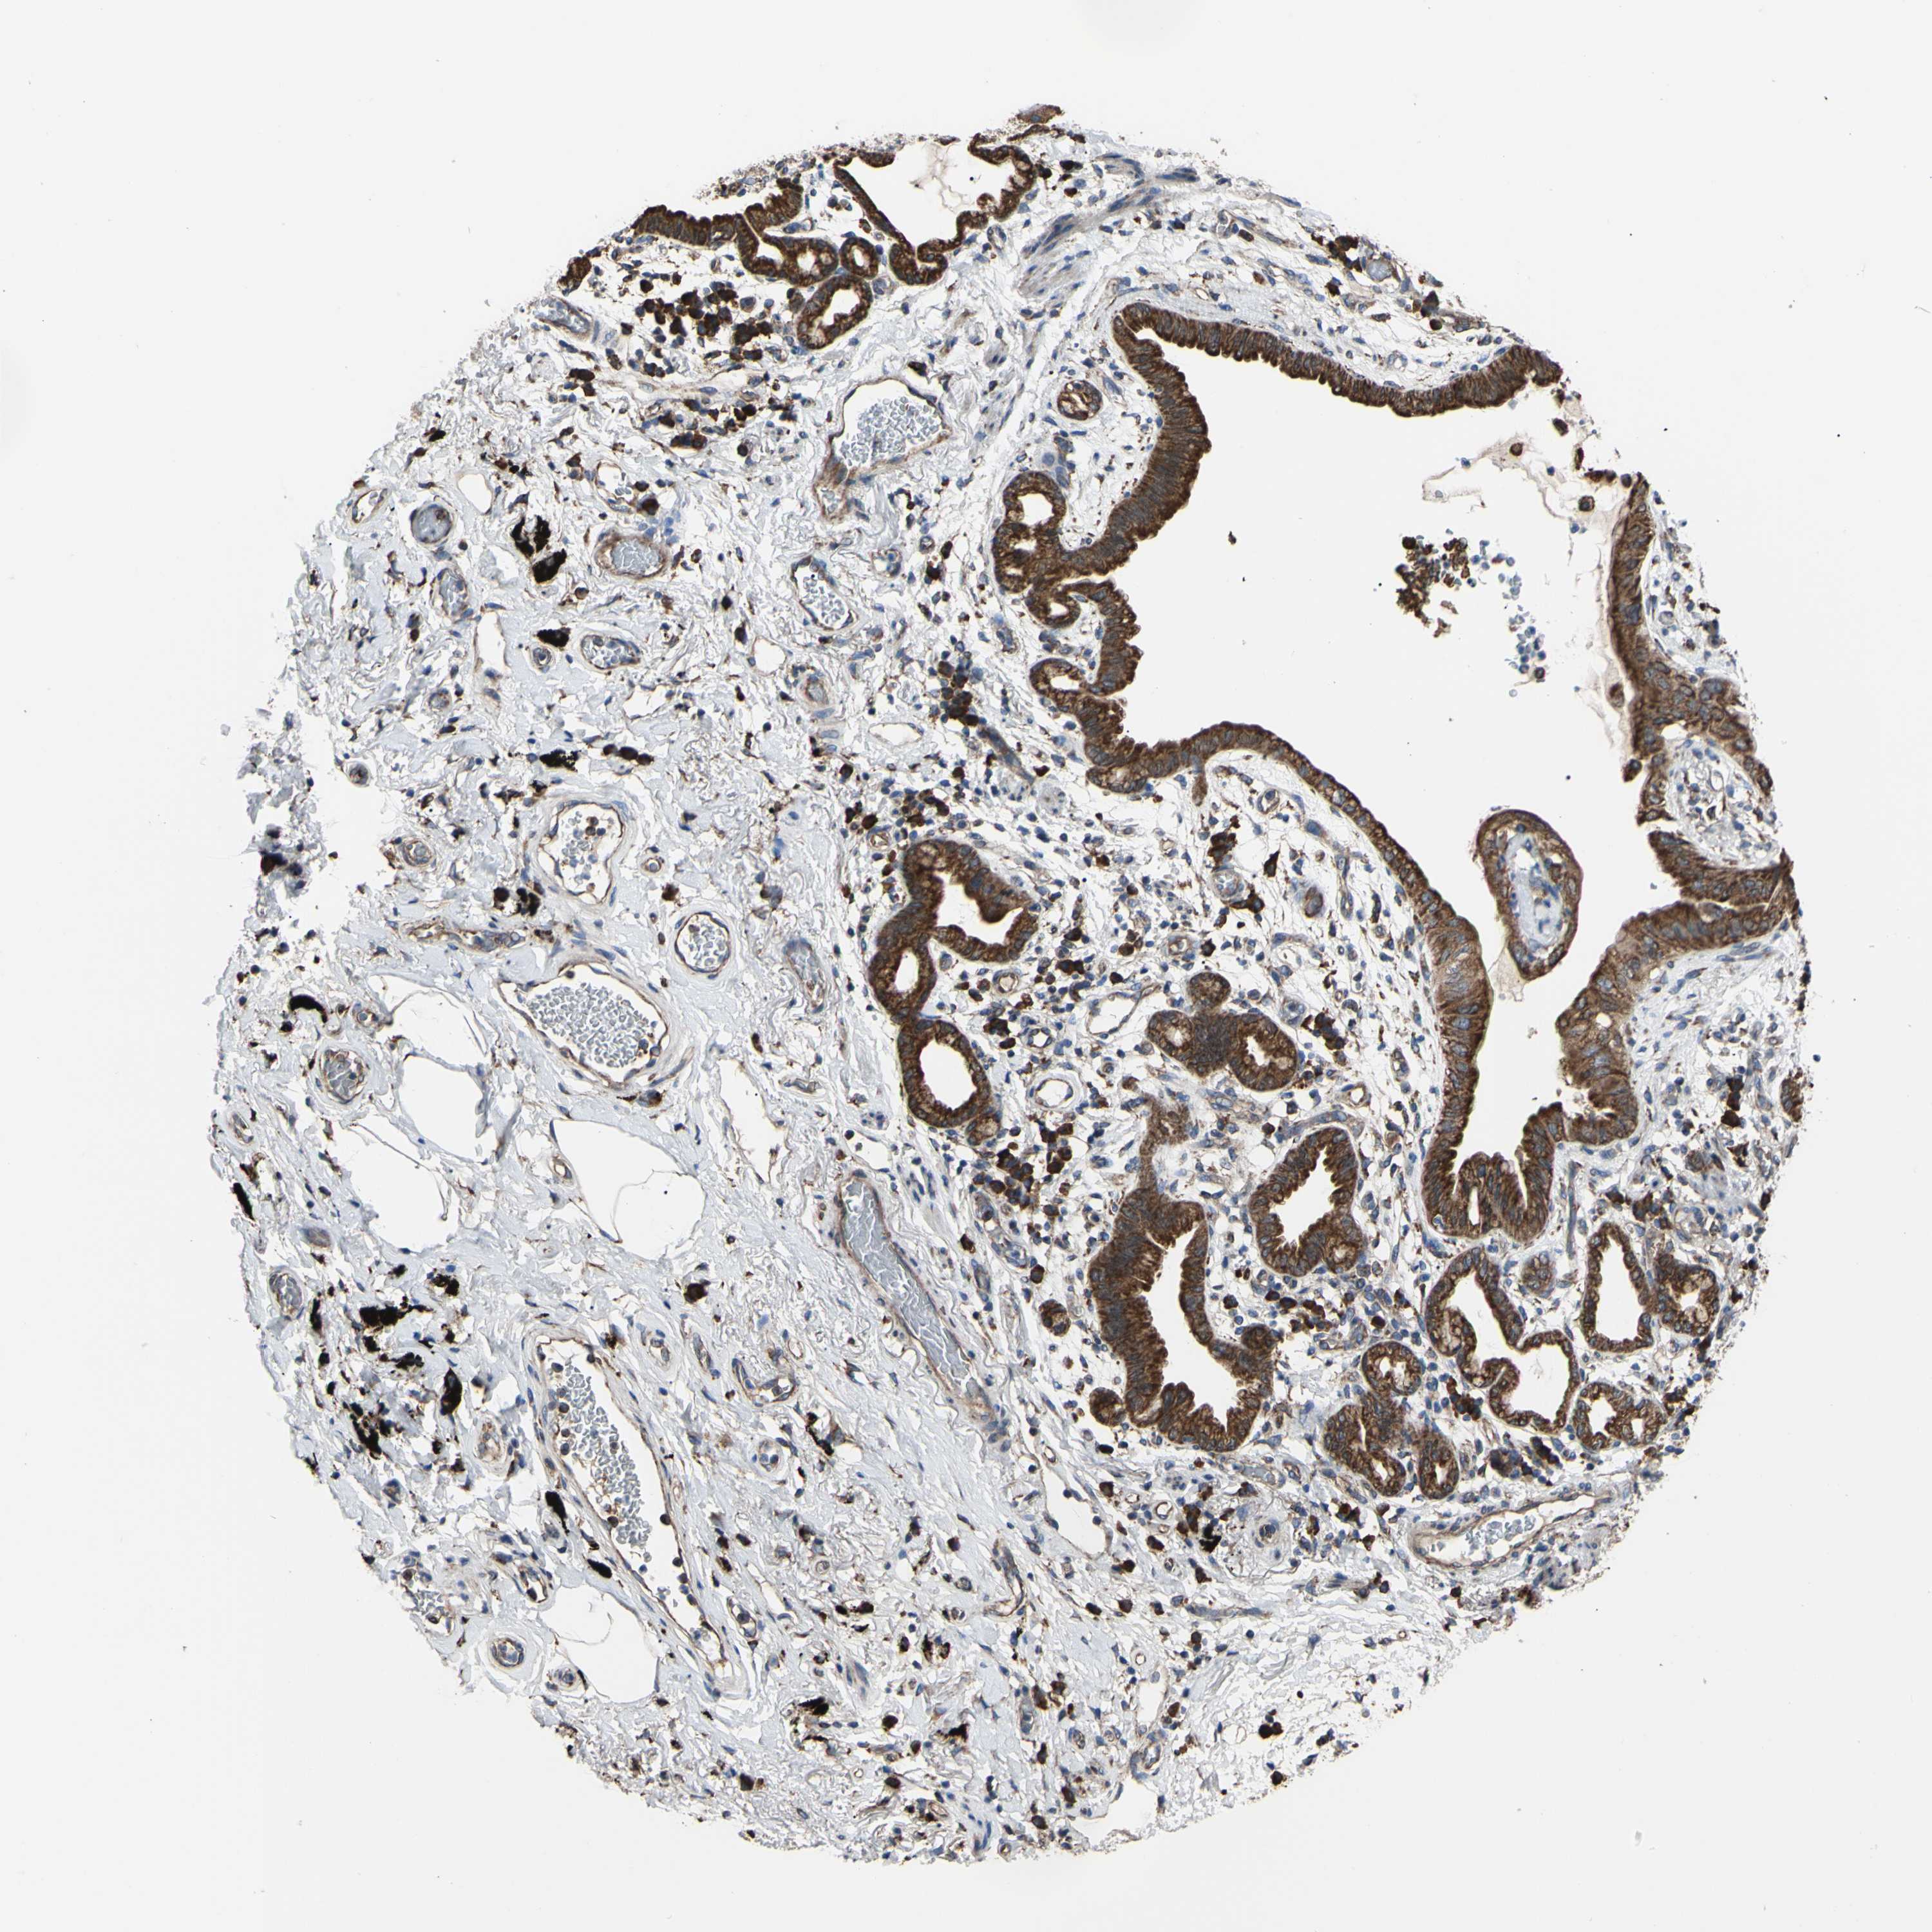

LUNG ADENOCARCINOMA (VALIDATION) - Interactive survival scatter ploti

The Survival Scatter plot shows the clinical status (i.e. dead or alive) for all individuals in the patient cohort, based on the same data that underlies the corresponding Kaplan-Meier plots. Patients that are alive at last time for follow-up are shown in blue and patients who have died during the study are shown in red.

The x-axis shows the expression levels (FPKM) of the investigated gene in the tumor tissue at the time of diagnosis. The y-axis shows the follow-up time after diagnosis (years). Both axes are complimented with kernel density curves demonstrating the data density over the axes. The top density plot shows the expression levels (FPKM) distribution among dead (red) and alive patients (blue). The right density plot shows the data density of the survived years of dead patients with high and low expression levels respectively, stratified using the cutoff indicated by the vertical dashed line through the Survival Scatter plot. This cutoff is automatically defined based on the FPKM cutoff that minimizes the p-score. The cutoff can be changed by dragging the vertical line or by entering a cutoff value in the square labeled "Current cut-off".

Under the Survival Scatter plot the p-score landscape (black curve; left axis) is shown together with dead median separation (red curve; right axis). Dead median separation is the difference in median mRNA expression between patients who have died with high and low expression, respectively. It is calculated as follows: median FPKM expression of dead patients with high expression - median FPKM expression of dead patients with low expression. This is intended to aid the user in visually exploring custom cutoffs and the associated p-scores and dead median separation.

Individual patient data is displayed and can be filtered by clicking on one or more of the category buttons on the top of the page. Categories describing expression level and patient information include: high, low, alive, dead, female, male and tumor stages. The scale of the x-axis can be toggled between linear and log-scale by clicking on the "x log" button. Mouse-over function shows TCGA ID, patient information and mRNA expression (FPKM) for each patient.

& Survival analysisi

Kaplan-Meier plots summarize results from analysis of correlation between mRNA expression level and patient survival. Patients were divided based on level of expression into one of the two groups "low" (under cut off) or "high" (over cut off). X-axis shows time for survival (years) and y-axis shows the probability of survival, where 1.0 corresponds to 100 percent.

BMF is not prognostic in Lung Adenocarcinoma (validation)

Best expression cut offi

Based on the FPKM value of each gene, patients were classified into two groups and association between prognosis (survival) and gene expression (FPKM) was examined. The best expression cut-off refers the FPKM value that yields maximal difference with regard to survival between the two groups at the lowest log-rank P-value. Best expression cut-off was selected based on survival analysis .

When clicking on this number, the vertical dashed line indicating cut-off, the interactive survival plot, and the Kaplan-Meier curve will be adjusted to show results based on the best expression cut-off.

: 23.52

Median expressioni

Median expression refers to the median FPKM value calculated based on the gene expression (FPKM) data from all patients in this dataset. When clicking on this number, the vertical dashed line indicating cut-off, the interactive survival plot, and the Kaplan-Meier curve will be adjusted to show results based on the median expression.

: N/A

Median follow up timei

Median follow up time refers to the median time (years) after diagnosis with this type of cancer, based on clinical data from all patients in this dataset.

P scorei

Log-rank P value for Kaplan-Meier plot showing results from analysis of correlation between mRNA expression level and patient survival.

N/A

5-year survival highi

5-year survival for patients with higher expression than the expression cutoff.

For melanoma and glioma, 3-year survival is shown.

5-year survival lowi

5-year survival for patients with lower expression than the expression cutoff.

TCGA RNA samplesi

RNA-seq data is reported as average FPKM (number Fragments Per Kilobase of exon per Million reads), generated by the The Cancer Genome Atlas (TCGA) .

Normal distribution across the dataset is visualized with box plots, shown as median and 25th and 75th percentiles. Points are displayed as outliers if they are above or below 1.5 times the interquartile range. FPKM values of the individual samples are presented next to the box plot.

Average pTPM 23.2

Number of samples 105